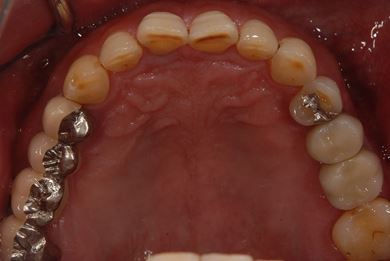

インプラントの症例写真 IMPLANT

抜歯即日スピードインプラント治療

| 治療方針 | 抜歯と同時にインプラント埋入を行い、治療期間を短縮する。 | ||||||||||||||||||||||||||||||||

| 治療内容 | インプラント2本(抜歯即日スピードインプラント) | ||||||||||||||||||||||||||||||||

| 総治療費 | 456,750円 | ||||||||||||||||||||||||||||||||

| 治療期間 | 10ヶ月 |